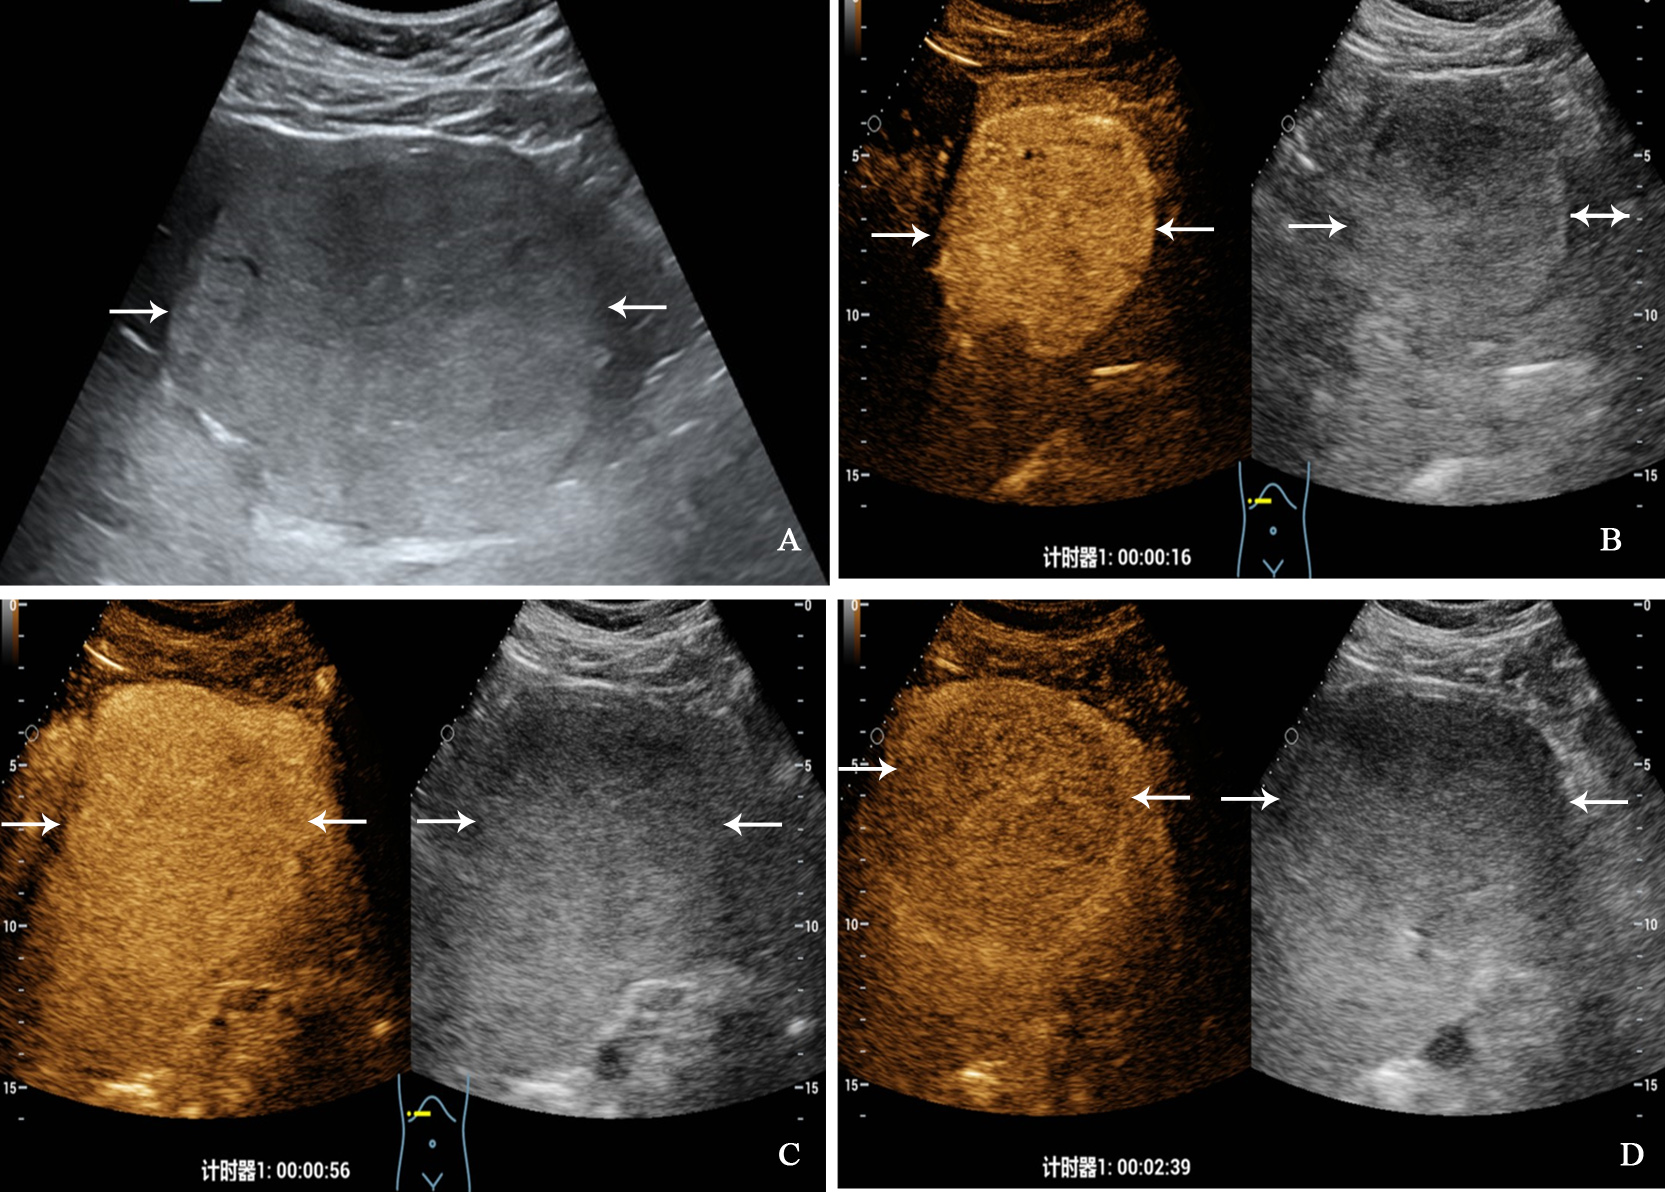

Figure 3

A 32-year-old man with primary neuroendocrine tumor. The patient had no underlying liver disease. Conventional ultrasound showed that a slightly hyperechoic tumor with largest diameter of 10.3 centimeters in left liver lobe (A). In the arterial phase of contrast-enhanced ultrasound, the tumor showed homogeneous hyperenhancement (B), and began washout at 56 seconds (C), hypoenhancement in the late phase (D).